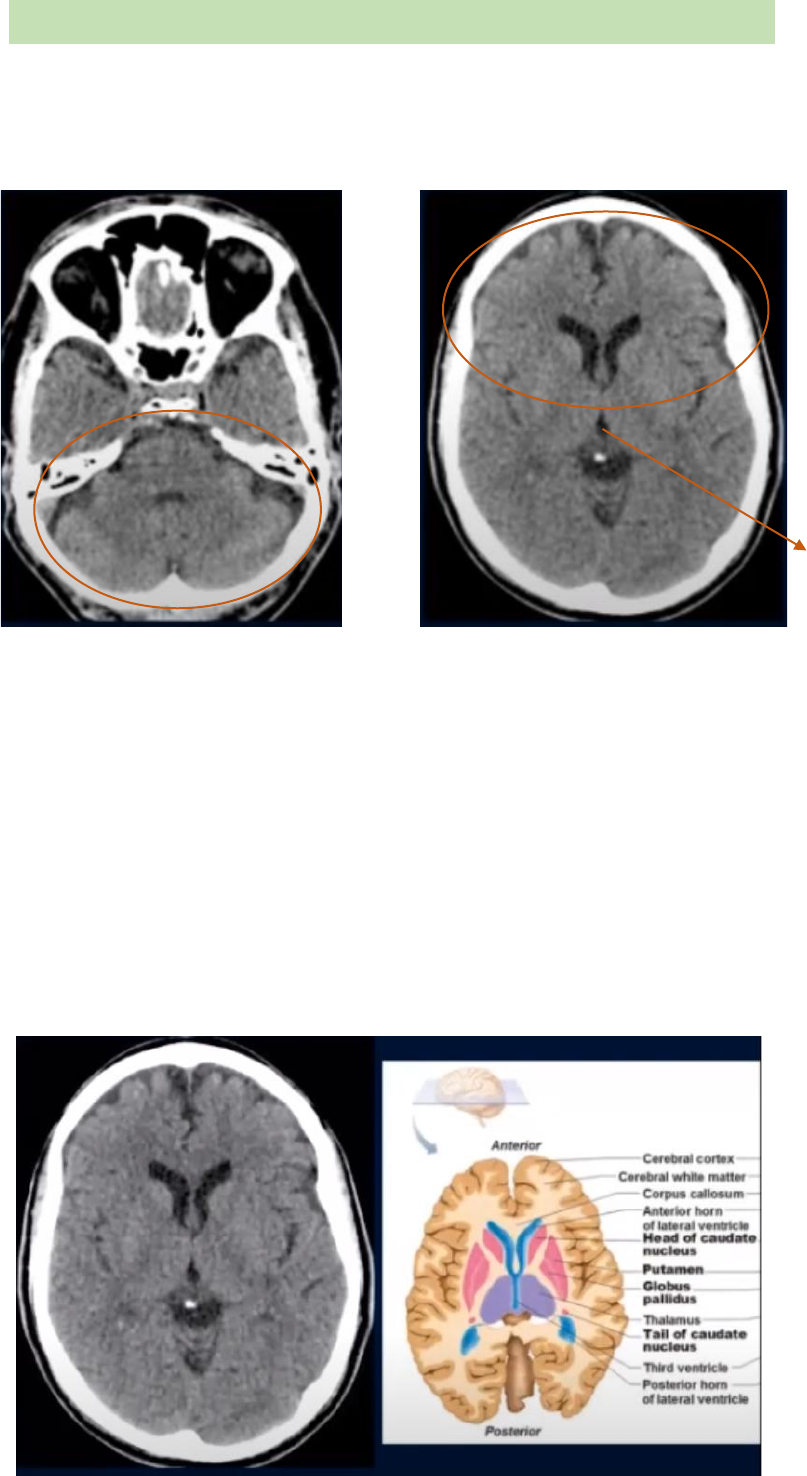

A tomografia computadorizada do crânio é feita em cortes axiais/ transversos. E na TC

áreas brancas são denominadas hiperdensas ou hiperatenuantes, e as áreas mais

escuras são denominadas hipodensas ou hipoatenuantes.

O crânio pode ser separado em dois compartimentos: (1) compartimento

supratentorial, que está acima da tenda do cerebelo e compreende os hemisférios

cerebrais; e (2) compartimento infratentorial, que está abaixo da tenda do cerebelo e

compreende o tronco encefálico e o cerebelo.

• Cérebro = hemisférios cerebrais (telencéfalo) + diencéfalo (compreende o

tálamo, epitálamo e hipotálamo). Na tomografia é possível visualizar o tálamo,

que encontra-se ao redor do terceiro ventrículo.

• Encéfalo = cérebro + tronco encefálico + cerebelo

CORTE COMPARTIMENTO

SUPRATENTORIAL

CORTE DA FOSSA POSTERIOR

COMPARTIMENTO INFRATENTORIAL

Terceiro

ventrículo

A faixa mais escurecida (forma de boomerang)

entre a cabeça do núcleo caudado e o lentiforme

é a cápsula interna (ramo anterior - joelho; e tem

o ramo posterior - entre o tálamo e o núcleo

lentiforme).

O cinza mais escuro após o núcleo lentiforme

compreende as cápsulas externas e extremas.

Deve-se lembrar que os tálamos não pertencem

aos gânglios da bases. Portanto quando fala

gânglios da bases de densidade normal, não

estamos nos referindo ao tálamo. Quando

compreender o tálamo + gânglios da base, usa-

se o termo de núcleos de substância cinzenta

(predomina corpos neuronais).

TÁLAMO

NÚCLEO LENTIFORME (Porção lateral - putâmen; porção medial – globo pálido). Na

TC não é possível visualizar essa divisão, assim pode chamar toda a estrutura de

núcleo lentiforme).

CABEÇA DO NÚCLEO CAUDADO

Ventrículo lateral

Direito e esquerdo

SULCO LATERAL OU FISSURA SILVIAN

JOELHO DO CORPO CALOSO

Nesse corte tomográfico

mais inferior vemos o bulbo

e os hemisférios cerebelares

(direito e esquerdo). O bulbo

compõe o tronco encefálico

(formado pelo bulbo, ponte

e mesencéfalo) Nessa

imagem, é possível visualizar

o bulbo, e logo atrás dele há

uma estrutura de densidade

líquida.

Em um corte mais superior

ainda é possível visualizar o

bulbo e os hemisférios. Bem

como, o cerebelo, mais

especificamente, o vermis

cerebelar na região da linha

média.

Ainda nesse corte, já na compartimento supratentorial é possível visualiza os polos dos

lobos temporais.